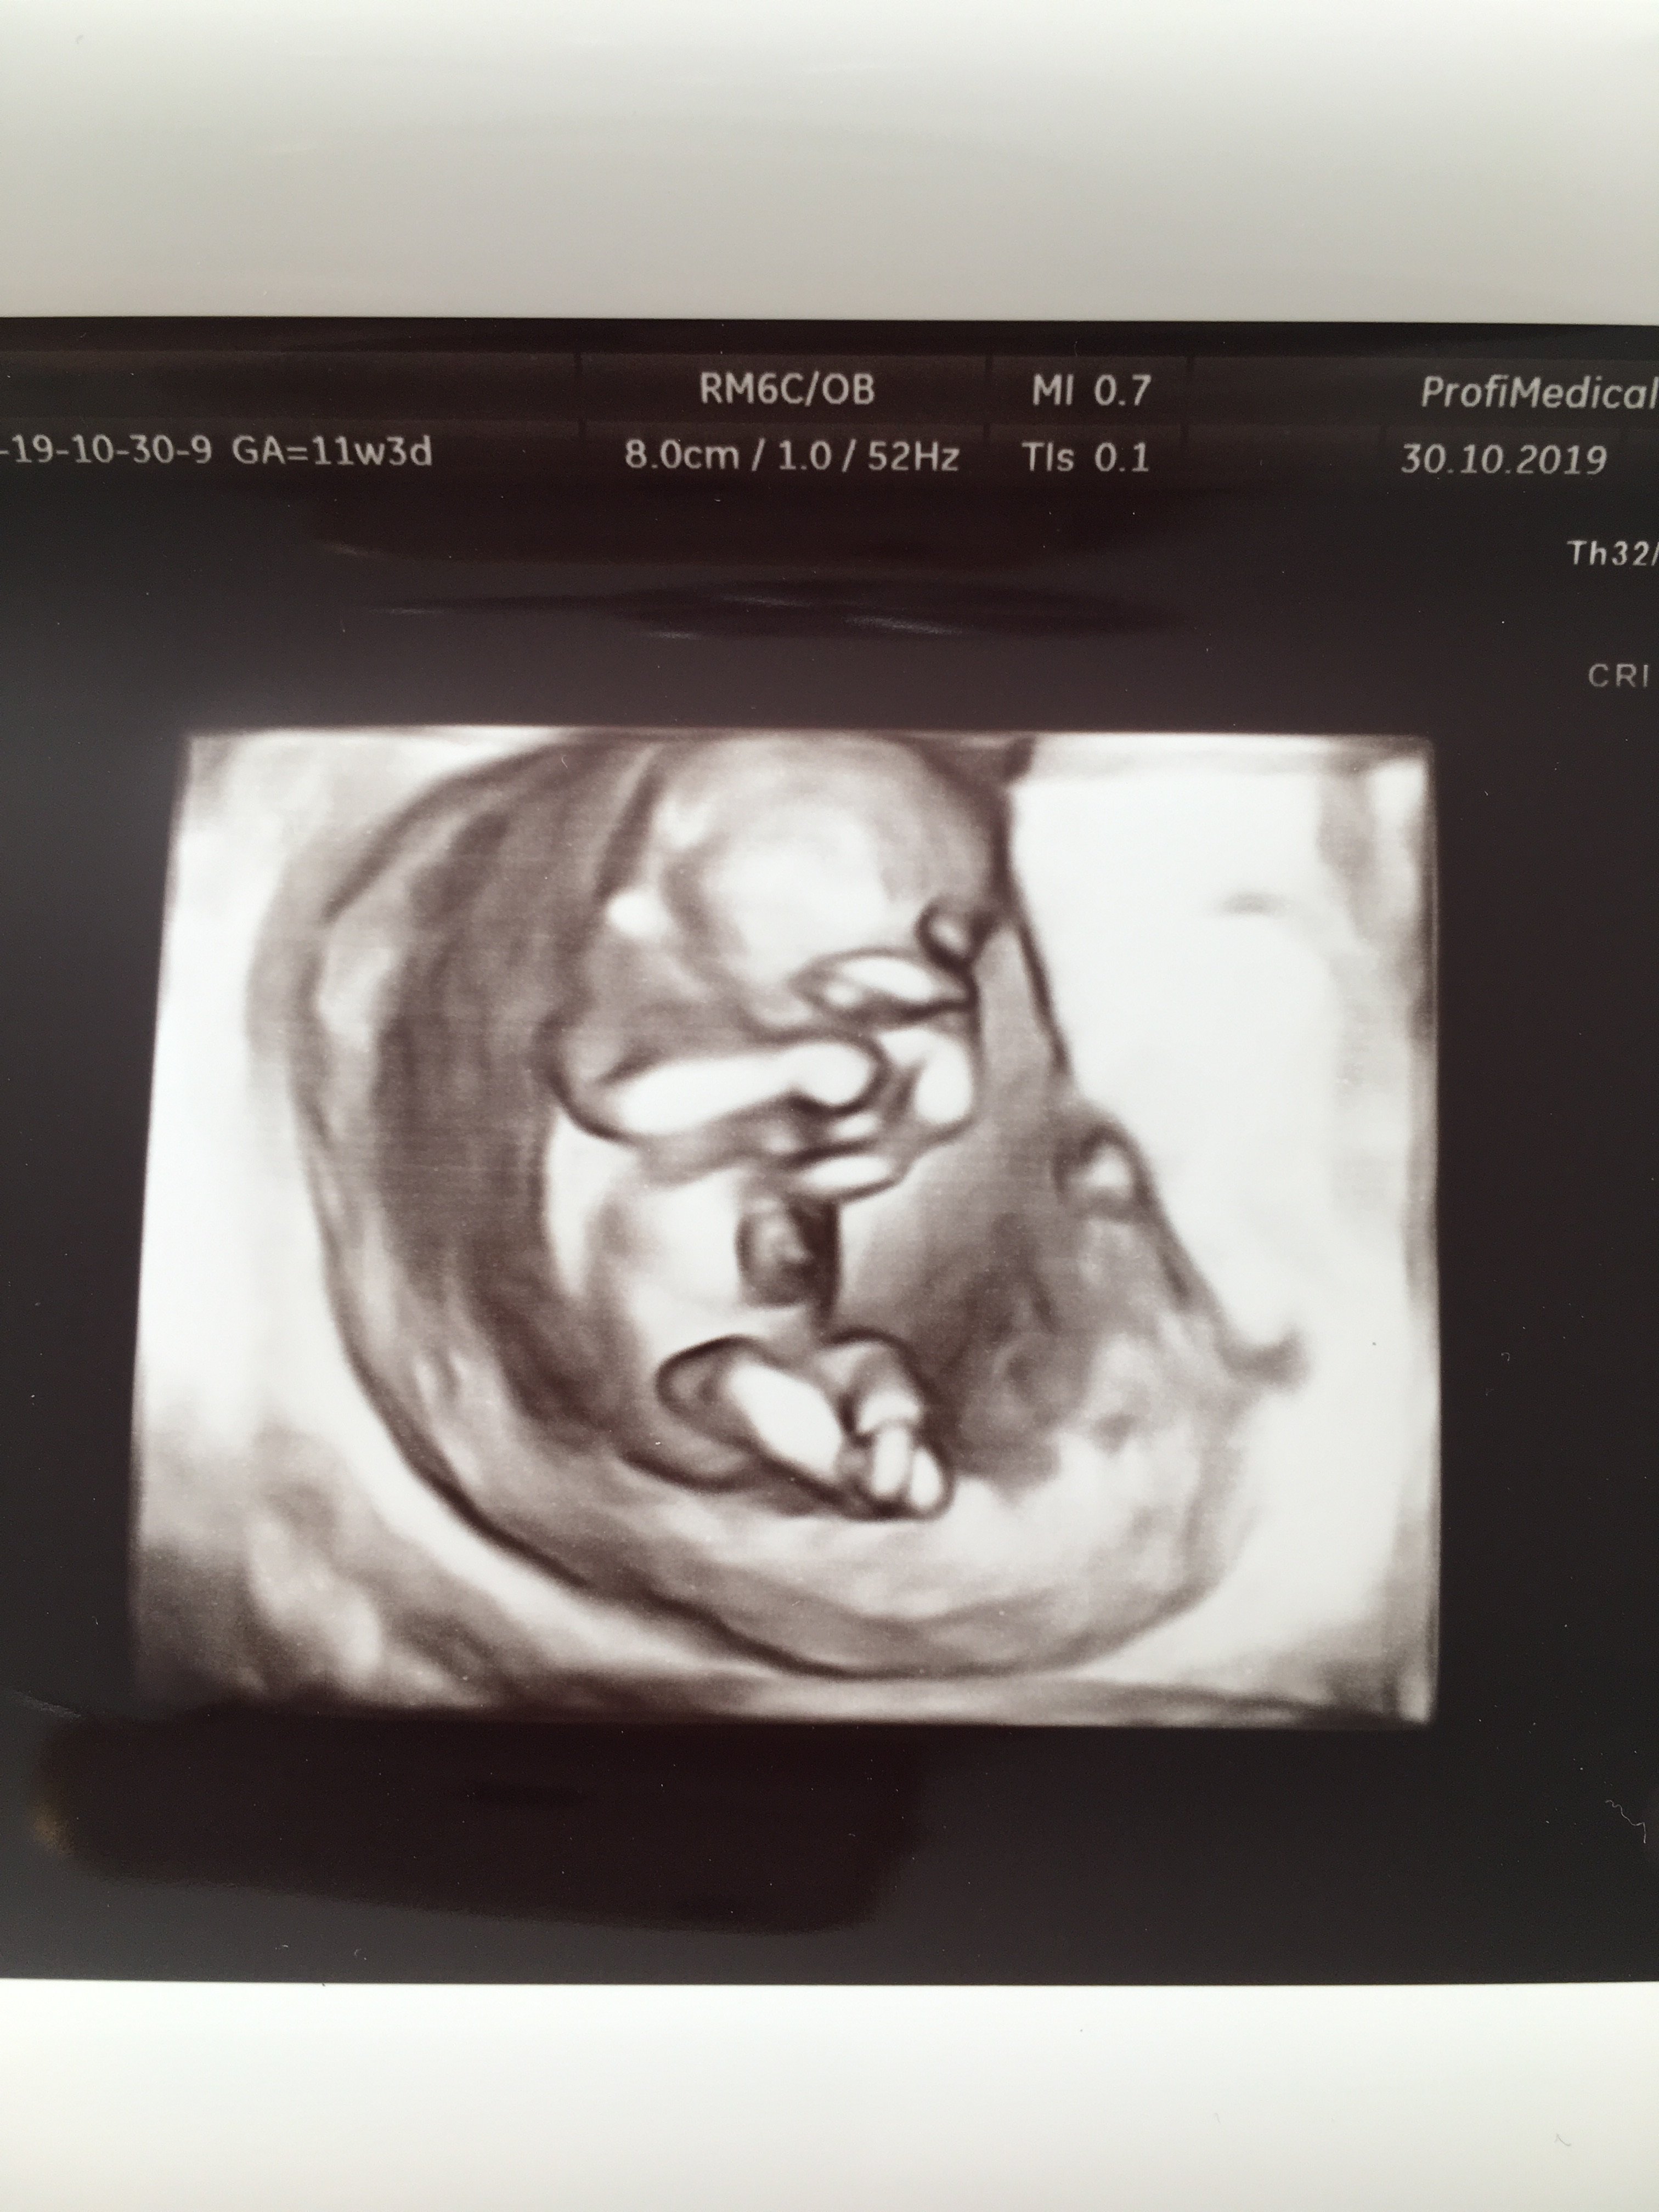

Moja wczorajsza wizyta ze zwyklego usg przekształciła się całkowicie niespodziewanie w prenatalne

Bo ten sam lekarz miał mi je robic, ale dopiero za 2 tyg. I chyba trochę chciał mieć mnie już z głowy, a trochę obawa była, ze dzidzia może byc już za duża, jak poczekam do ustalonego terminu. A ja byłam chyba w takim szoku, ze nie zdazylam bardzo protestować. Z usg jest wszystko Ok, czekam jeszcze za wyniki z krwi.

I póki co lekarz nie zobaczył nic dyndającego między nóżkami - a przyznaje, ze marze o dziewczynce

A to moja dzidzia[emoji3590][emoji3590]